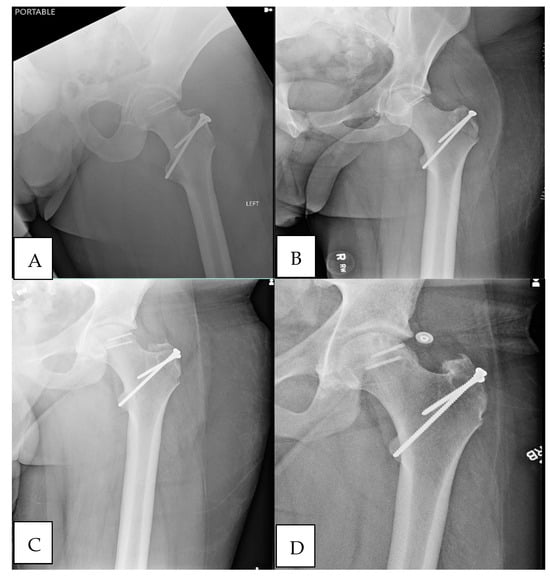

A 21-year-old male presented following a motorcycle collision with the chief complaint of left hip pain. The patient had a BMI of 36.7 and no previous history of smoking. He denied previous orthopedic injuries or surgeries. Imaging demonstrated a posterior-inferior dislocation with lateral impaction of the left femoral head weight–bearing surface into the acetabulum (Figure 1A). The left hip was closed reduced, and a distal femoral traction pin was placed (Figure 1B). On his initial examination, the patient was neurovascularly intact with no other orthopedic injuries. An anteroposterior (AP) radiograph demonstrated a reduced left femoral head with a mildly displaced fracture of the lateral aspect of the left femoral head and a concomitant posterior acetabular wall fracture (Figure 1B). The injury was confirmed with a CT scan. The location of the femoral head osteochondral defect was in the weight-bearing region circumferential to and above the fovea, suggesting a high likelihood for post-traumatic osteoarthritis if left untreated. Surgical intervention of the femoral head was indicated to reduce the likelihood of post-traumatic osteoarthritis. The patient was not a candidate for arthroplasty given his age and presumed improved outcomes with hip preservation treatment.

Figure 1. (A) Anterior-to-posterior radiograph of the pelvis demonstrating left posterior hip dislocation with impaction of the femoral head into the posterior wall. (B) Anterior-to-posterior radiograph of the pelvis post-reduction film demonstrating the suspected left femoral head and/or a posterior wall of the acetabulum fracture.

Figure 3. (A) Anterior-to-posterior radiograph of the left hip after open reduction internal fixation of the left femoral head osteochondral lesion. (B) Anterior-to-posterior radiograph of the left hip at 2 weeks following open reduction internal fixation of the left femoral head osteochondral lesion. (C) Anterior-to-posterior radiograph of the left hip at 8 weeks following open reduction internal fixation of the left femoral head osteochondral lesion. (D) Anterior-to-posterior radiograph of the left hip at 2 years following open reduction internal fixation of the left femoral head osteochondral lesion.